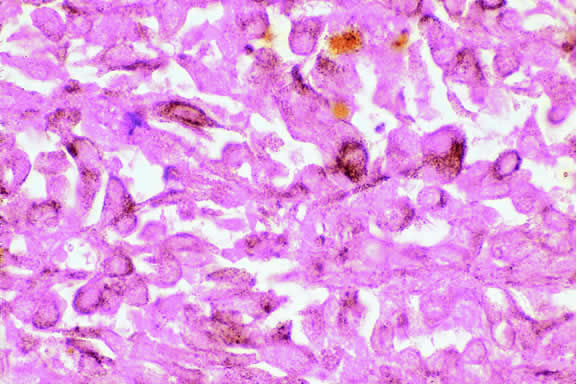

Choroidal melanomas produce abnormalities in the overlying retinal pigment epithelium including atrophy, hyperplasia, and the formation of drusen and drusenoid material.92 The overlying retina often shows photoreceptor loss and may develop cystoid edema. The latter tends to be more common in slower growing lesions, especially choroidal hemangiomas. After Bruch's membrane has ruptured, the vessels located in the mushrooming head of the tumor are often quite prominent, reflecting vascular stagnation caused by the compression at the waist of the tumor (see Fig. 22). Aggregates of macrophages that have ingested periodic acid-Schiff (PAS)-positive lipofuscin pigment and melanin from the damaged retinal pigment epithelium can be found in the subretinal fluid (Figs. 39 to 41). These are evident ophthalmoscopically as clumps of orange pigment that serve as a clinical marker for an actively growing neoplasm.80,81

Fig. 39. Juxtapapillary melanoma with orange pigment. Orange pigment is a clinical marker for an actively growing tumor.

Fig. 41. Orange pigment. Orange pigment is comprised of aggregates of macrophages that have phagocytized periodic acid-Schiff (PAS)-positive lipofuscin and melanin pigment released by retinal pigment epithelial cells that have been disrupted by the actively growing tumor. (Periodic acid-Schiff, × 100.)